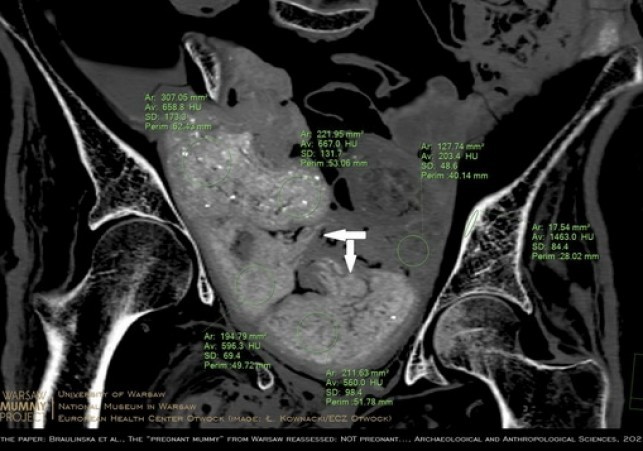

Nie płód, ale kilka zawiniątek znajduje się w miednicy mumii kobiety prezentowanej w Muzeum Narodowym w Warszawie - dowodzi zespół naukowców. W jednym z pakunków umieszczono zapewne zmumifikowany organ. Rzekoma ciąża to efekt komputerowej iluzji i błędów interpretacji - uważają badacze.

W lipcu 2022 ukazała się bogato ilustrowana publikacja w "Archeological and Anthropological Sciences" (DOI: 10.1007/s12520-022-01598-z), w której inny zespół badaczy z WMP dowodzi, że zmumifikowana kobieta z pewnością nie zawiera w sobie płodu. Świadczą o tym przede wszystkim obrazy precyzyjnie zrekonstruowanej zawartości miednicy oraz wyniki badań porównawczych starożytnych płodów egipskich.

Naukowcy ustalili, że w miednicy wcale nie ma płodu - jak sugerowali autorzy doniesienia z 2021 r. - ale cztery pakunki.

"Umieścili je tam starożytni balsamiści. W zawiniątkach znajduje się najprawdopodobniej co najmniej jeden zmumifikowany organ zmarłej. To znana praktyka w starożytnym Egipcie" - podkreśliła Braulińska. W pozostałych być może są fragmenty ciała lub inne pozostałości po procesie mumifikacji. Jest też inna opcja - balsamiści umieszczali w mumiach zawiniątka po to, aby utrzymać kształt ciała po procesie mumifikacji.

To właśnie trzy z czterech pakunków w miednicy poprzedni zespół zinterpretował jako płód. O tym, że kobieta nie była w ciąży, świadczą też ilościowe pomiary gęstości radiologicznych, a także wzajemne relacje geometryczne pakunków oraz porównawcza charakterystyka materiałów znajdujących się wewnątrz mumii - argumentują badacze w nowo opublikowanym artykule.

Autorzy nowego artykułu podkreślają, że wykorzystali te same dane uzyskane metodą tomografii komputerowej, co poprzedni zespół oraz m.in. to samo oprogramowanie.

"Wykazaliśmy w ten sposób, jak bardzo analizy efektów trójwymiarowych i ich interpretacja zależą od umiejętności użytkownika oprogramowania, który może osiągnąć doskonałe efekty wizualizacji również nie będąc radiologiem" - powiedział PAP dr Kownacki.

Na potrzeby najnowszego opracowania wykorzystano możliwości analiz radiologicznych dostępne w Zakładzie Diagnostyki Obrazowej Europejskiego Centrum Zdrowia Otwock, m.in. unikalne medyczne oprogramowanie holograficzne dla systemów tzw. rzeczywistości mieszanej (ang. Mixed Reality), jak również radiologiczne rozwiązania serwerowe.